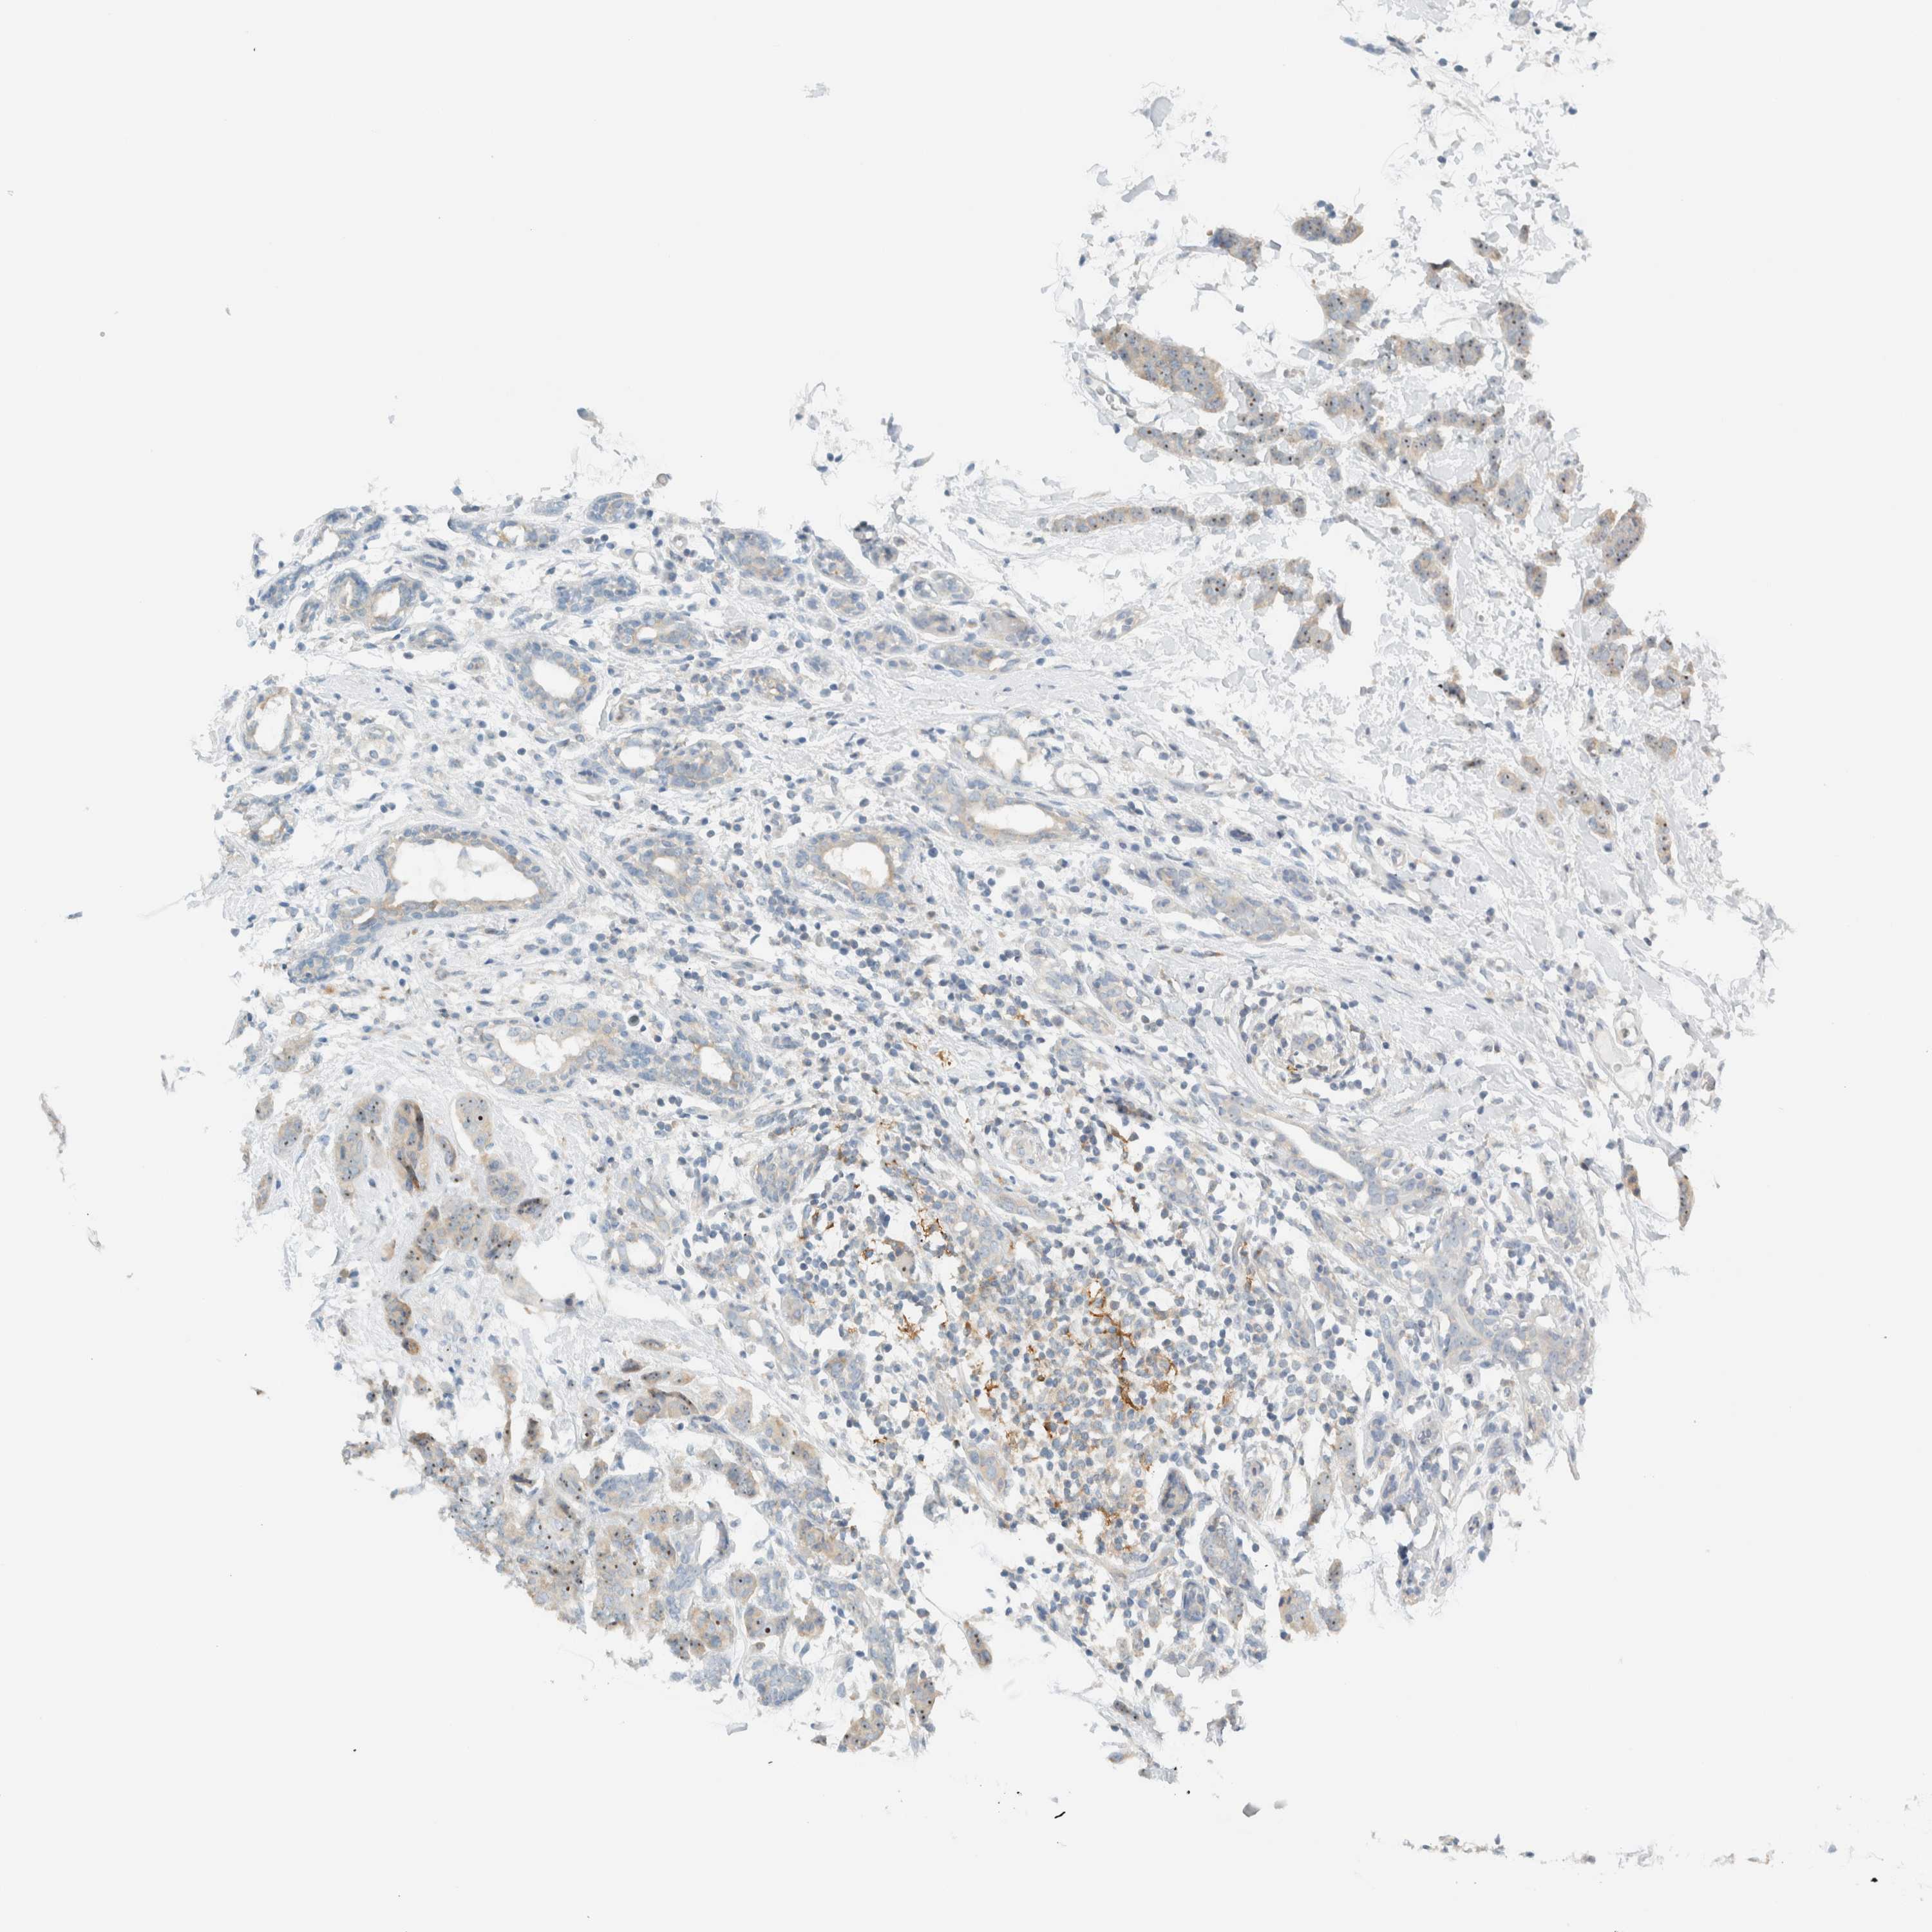

CANCER BREAST CANCER Show tissue menu

BRCA TCGA BRCA VALIDATION PROTEIN EXPRESSION